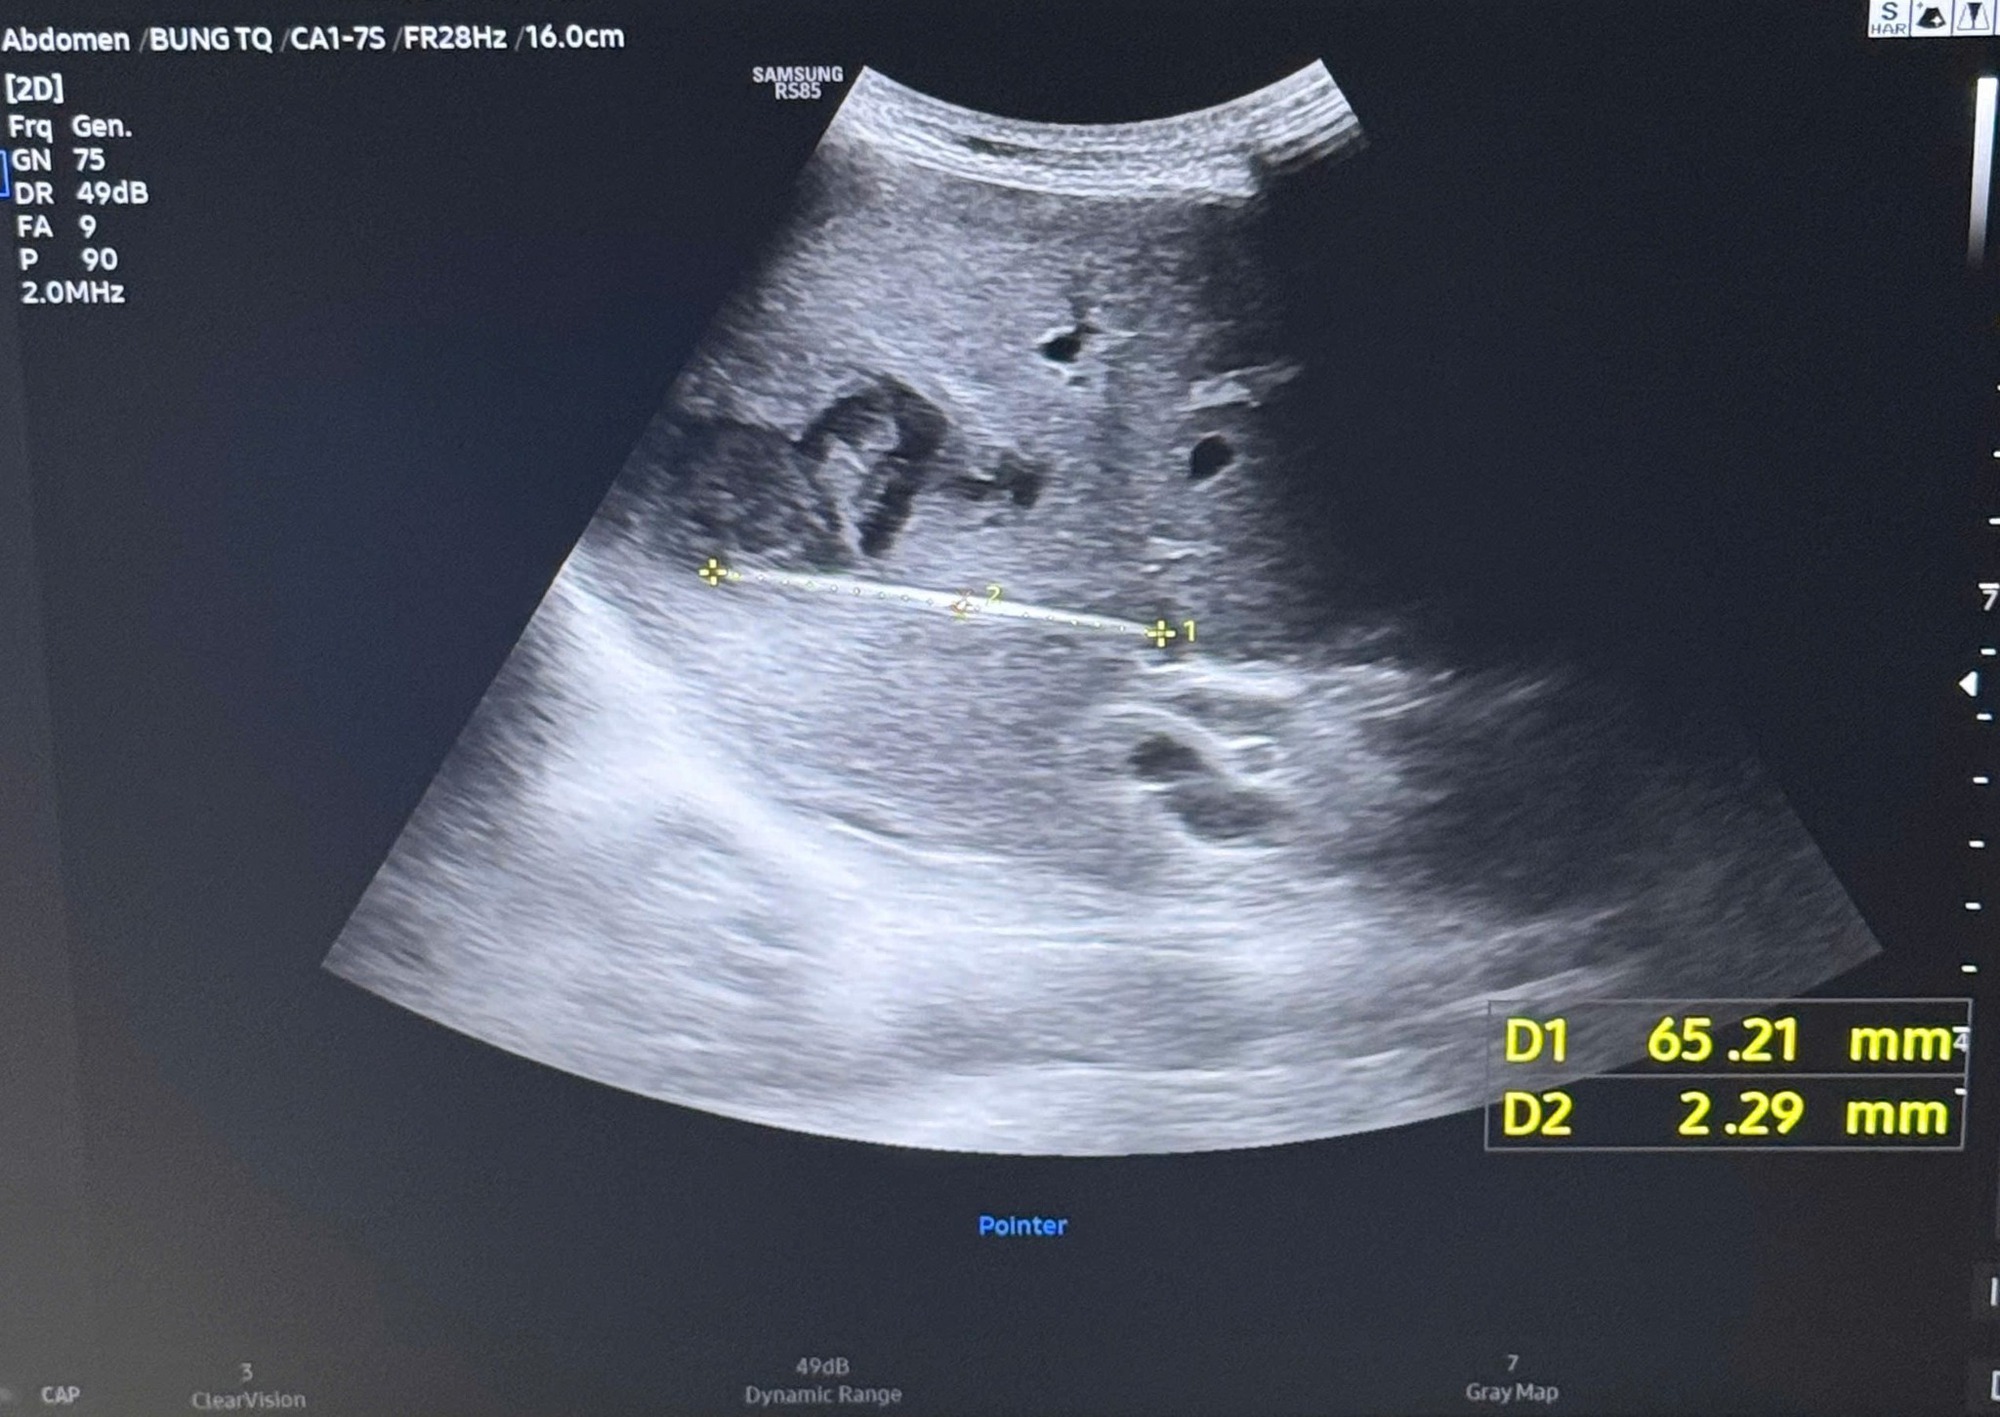

Cây tăm được bác sĩ gắp ra (bên trái) và hình ảnh cây tăm qua siêu âm (bên phải)

Khi tiến hành siêu âm chi tiết hơn, ê-kíp điều trị phát hiện một dị vật cản quang xuyên trong nhu mô gan, dài khoảng 6-7cm. Kết quả chụp cắt lớp vi tính (CT scan) ổ bụng sau đó xác định có một dị vật dạng que dài nằm hoàn toàn trong gan, kèm theo ổ áp xe sâu.